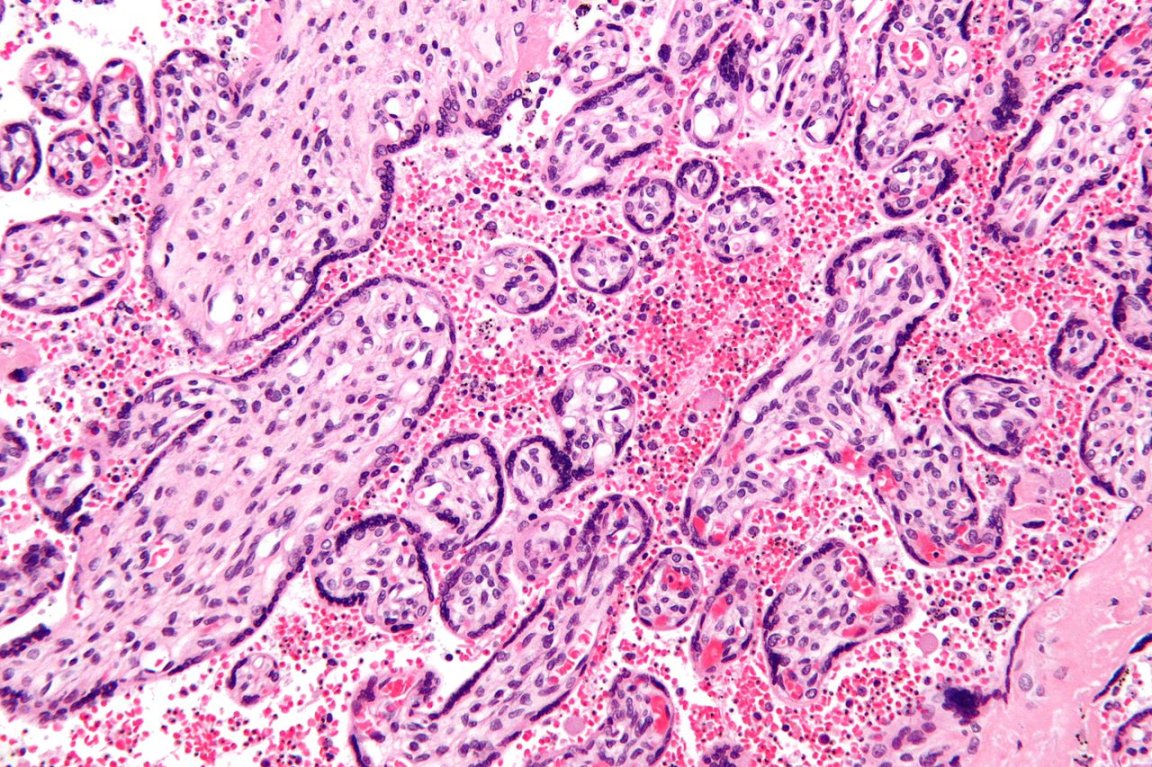

The recent study, published in the journal Science, found that a specific type of gut bacteria can actually leave our gastrointestinal system and cause trouble elsewhere in the body. Furthermore, the researchers found that when that bacterium, Enterococcus gallinarum, relocates to other organs (like the lymph nodes, liver, and spleen) it appears to trigger an inflammatory response.

That response, such as the release of antibodies, seems to be linked to the development of autoimmune conditions like lupus.

The team started by demonstrating the link in mice who had been genetically engineered to be susceptible to developing autoimmune diseases. They then confirmed that human patients with autoimmune diseases often have E. gallinarum in their livers.